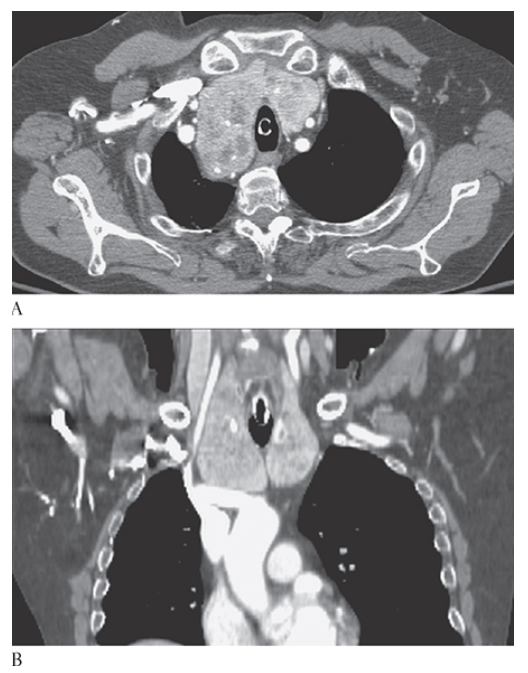

What is A

Thyroid Goiter. Axial and coronal

What is B

Thyroid Goiter. Axial CECTs show an enlarged heterogeneously enhancing thyroid gland with multiple low-attenuation cysts and calcifications, respectively.